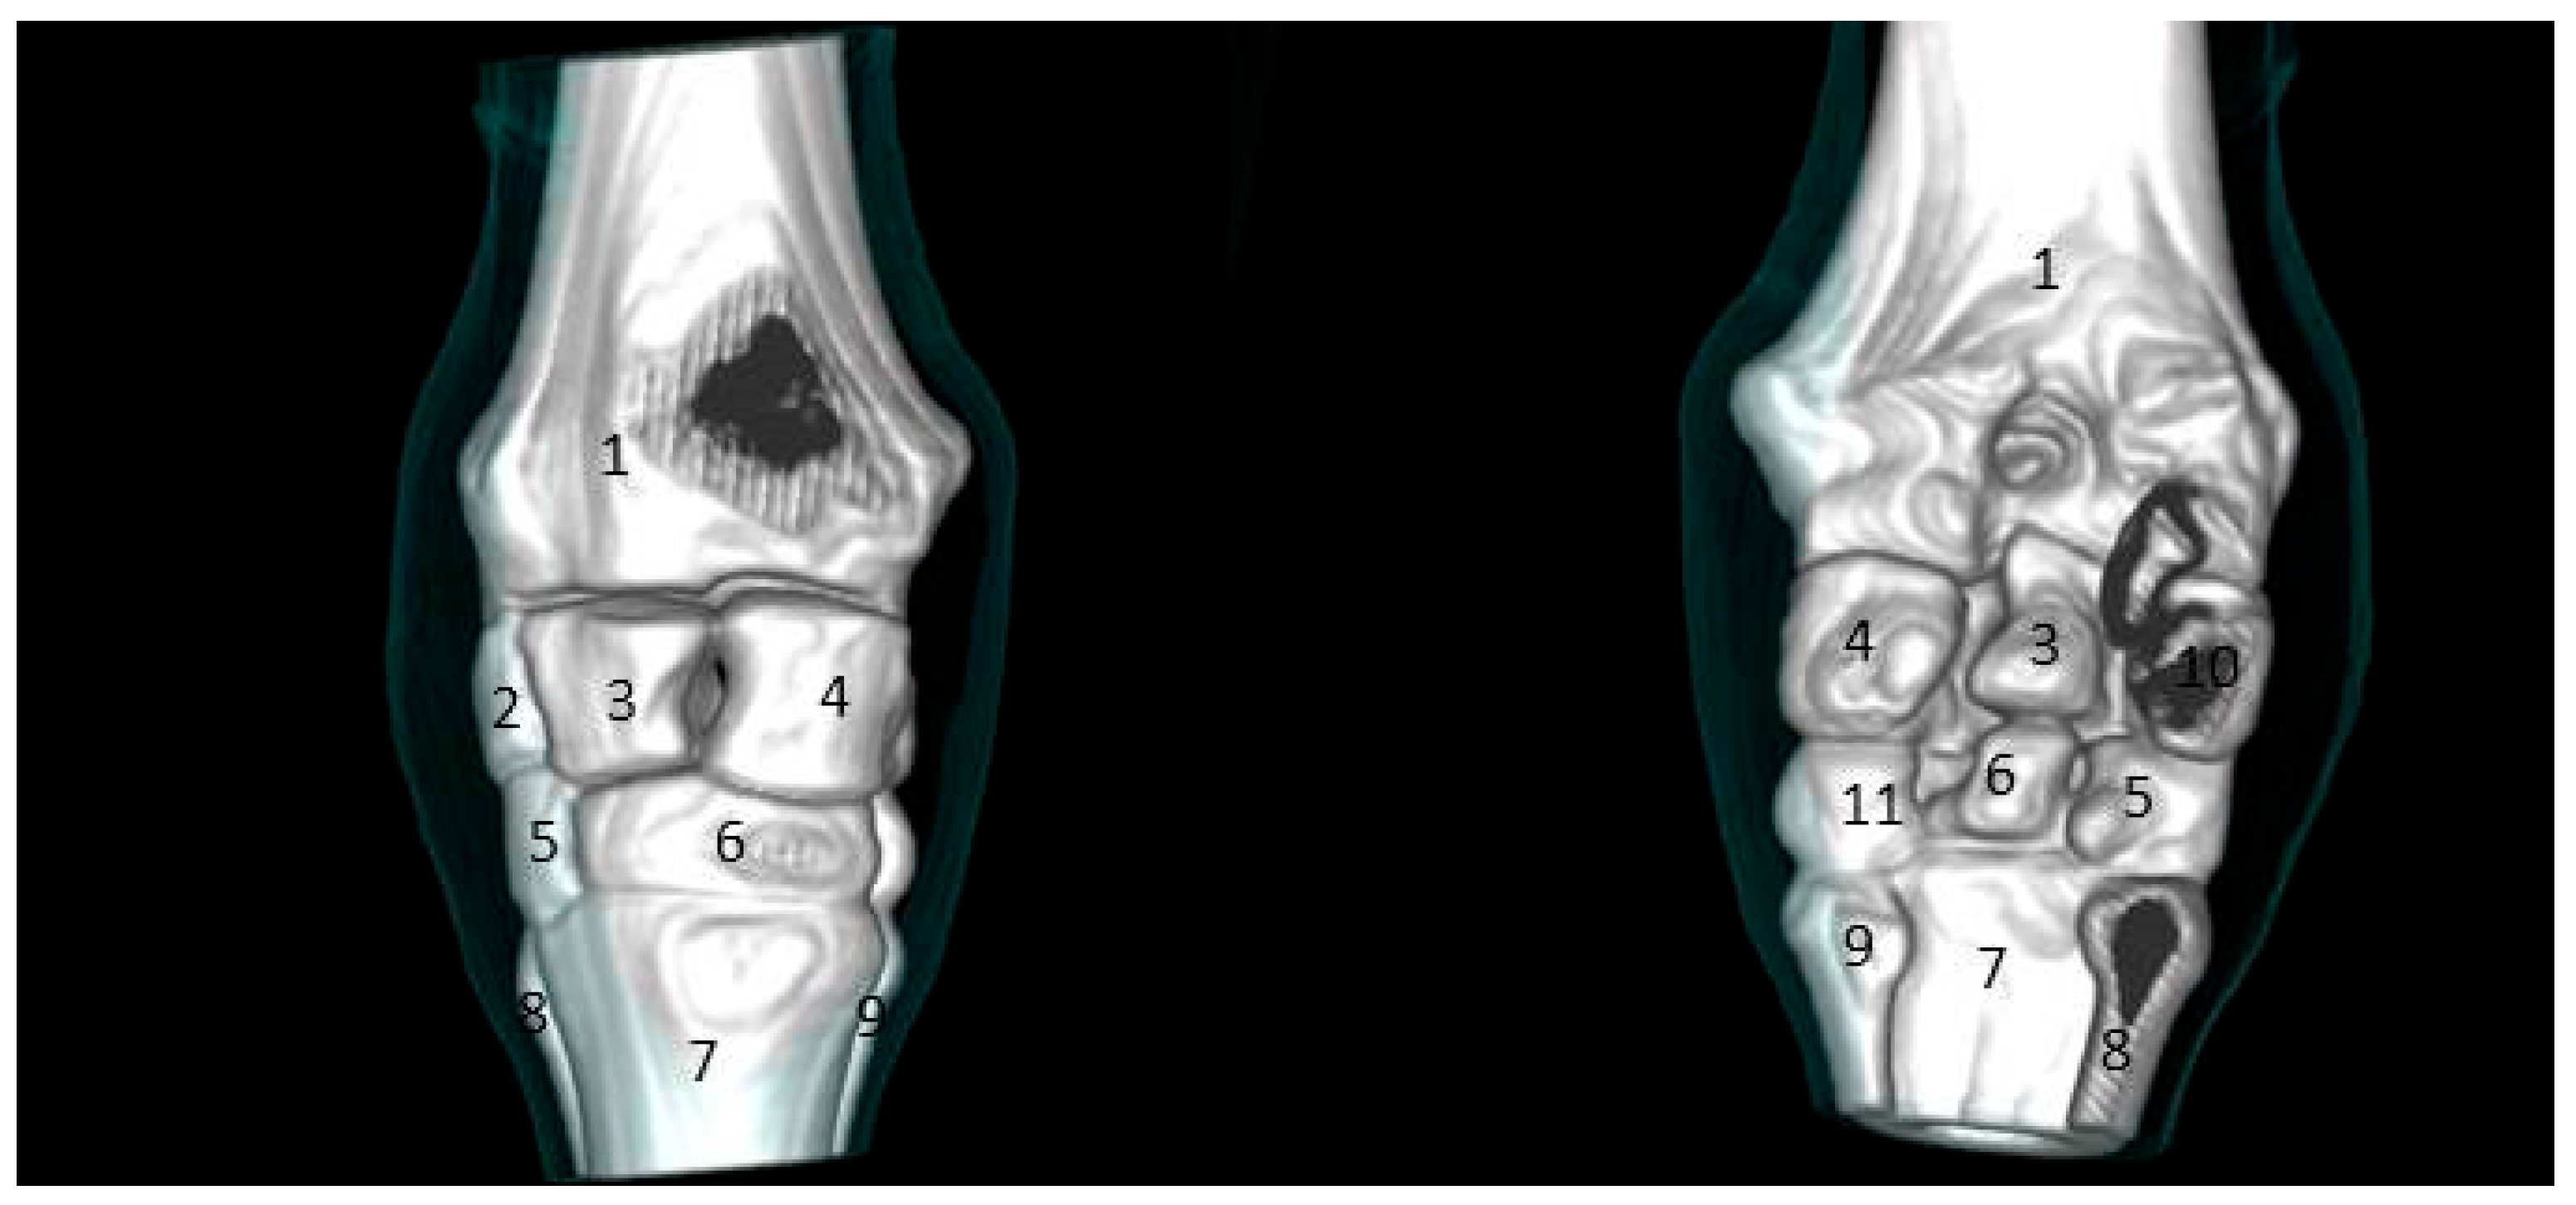

3.2. CT Findings

3.2.1. Sagittal and 3D Scan

3.2.2. Transverse Scan